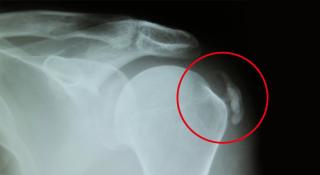

Verkalking van de schouder wordt veroorzaakt door een ontsteking in één of meerdere rotator cuff pezen. De rotator cuff bestaat uit vier spieren die rond het schoudergewricht lopen en via pezen zijn vastgehecht aan de kop van de ‘bol’ van het schoudergewricht.

Wanneer deze pezen ontsteken, komt er kalk vrij wat na een tijdje tot een ophoping van kalk kan leiden. Dit kan erg pijnlijk zijn.